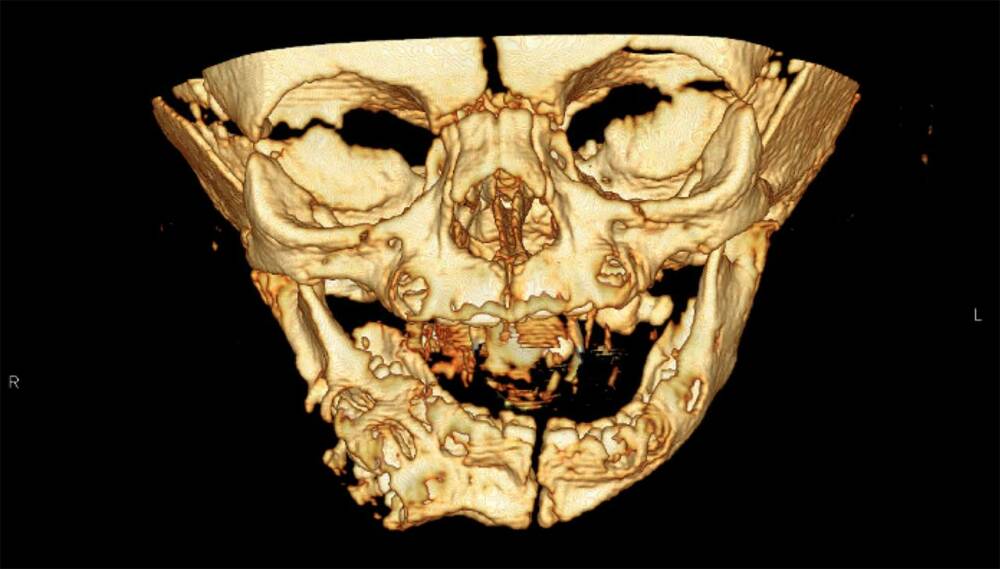

Второй рот у младенца не имел связи с пищеводом, но был сформирован. Наблюдались губы, зубы и даже иннервированный язык. Он также выделял жидкость, вероятно, слюну.

В 6 месяцев девочке сделали операцию по удалению лишнего органа. Для этого медики высверлили нижнюю челюсть и удалили оттуда лишние кости, из которых росли зубы второго рта. После успешной операции у ребенка в течение нескольких месяцев зажили швы, потому девочка могла полноценно принимать пищу. Однако, мышцы, двигающие правую часть нижней губы, у нее теперь не работают.